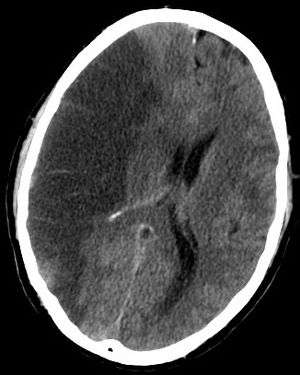

A stroke can be caused by a few different situations, but the basic result is the same. Blood flow to a section of the brain is stopped, which results in rapid depletion of oxygen and other nutrients in the starved section. The starved section of brain tissue quickly begins to die, and results in a lesion in the brain. The resulting lesion can be traced loss of various cognitive functions depending on the location and area of damage.[5]